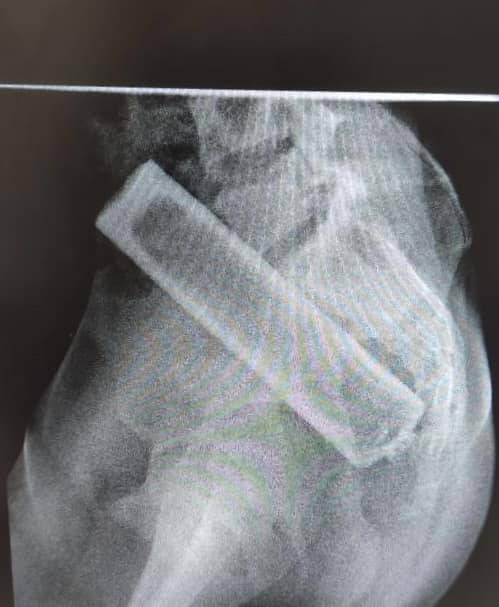

Один із останніх таких випадків стався з 16-річним хлопцем, у животі якого лікарі виявили вібратор. Три години вібратор продовжував працювати всередині пацієнта, приводячи до дискомфорту, болю в животі та кровотечі.